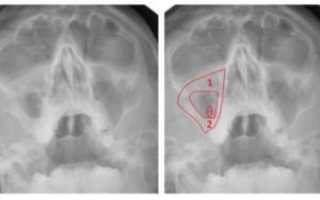

Также при пристеночном гайморите пациента обязательно направляют на рентген. Вот, что позволяет выяснить этот способ:

- Снижение пневматизации верхнечелюстного синуса.

- Состояние орбит глаз и лицевых костей.

- Пристеночное затемнение пазух.

Обычно после проведения рентгена никаких вопросов не остается. Но, если ситуация все еще остается не проясненной, назначают проведение компьютерной томографии. Это очень информативный метод диагностики. Благодаря КТ удается в деталях рассмотреть все структурные изменения пазух, выявить воспаление, уплотнение, деформацию и т. д.

- Пристеночное затемнение на снимке. Его можно заметить на рентгенограмме. Для подтверждения диагноза снимки делают минимум в двух проекциях. Разросшийся эпителий напоминает темные асимметричные пятна. Помимо этого, применяют КТ и МРТ.

Рентген – основной метод диагностики, когда есть подозрение на утолщение слизистой оболочки верхнечелюстных пазух